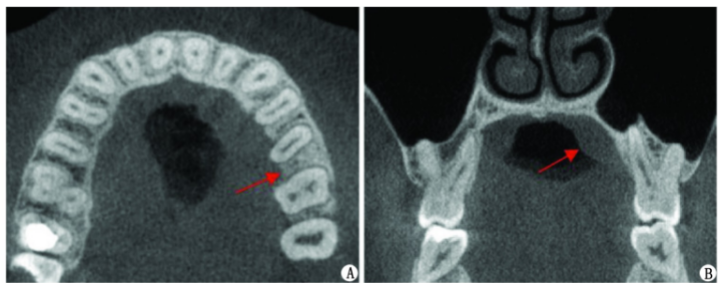

显微根尖手术联合引导组织再生术治疗左上前牙根尖囊肿1例及3年回访

病史摘要:43岁女性,因“左上前牙牙松动”就诊,左上前牙曾在外院行根管治疗,时间不详。否认心血管疾病、糖尿病等系统性疾病史,否认肝炎等传染性疾病、药物过敏及精神和心理病史。口腔卫生差。诊疗过程:口腔检查发现多颗牙齿存在不同程度的问题。根尖片和CBCT显示21、22根尖周有大面积阴影等情况。诊断为12继发龋、21和22慢性根尖周炎。治疗方案包括12充填治疗,21显微根管治疗,22显微